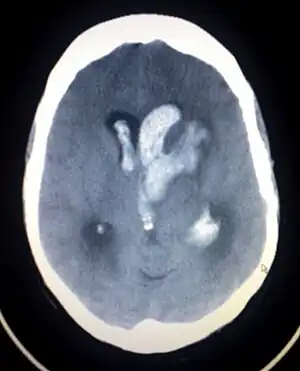

![]() Scanarea CT a unei sângerări intracerebrale spontane, care se scurge în ventriculii laterali | |

| Metodă de diagnostic | Scanare CT[1] |